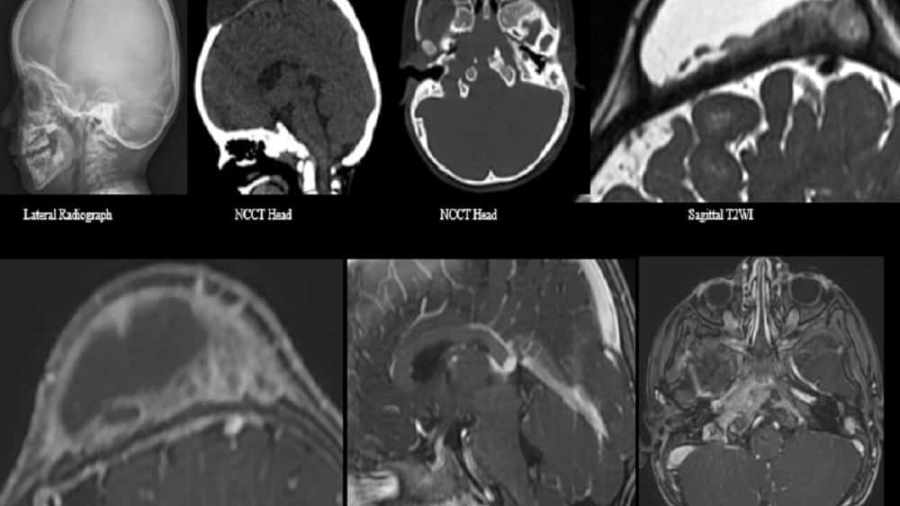

A 3-year-old male presented with nontender gradually progressive cystic swelling over the scalp for 9 months.